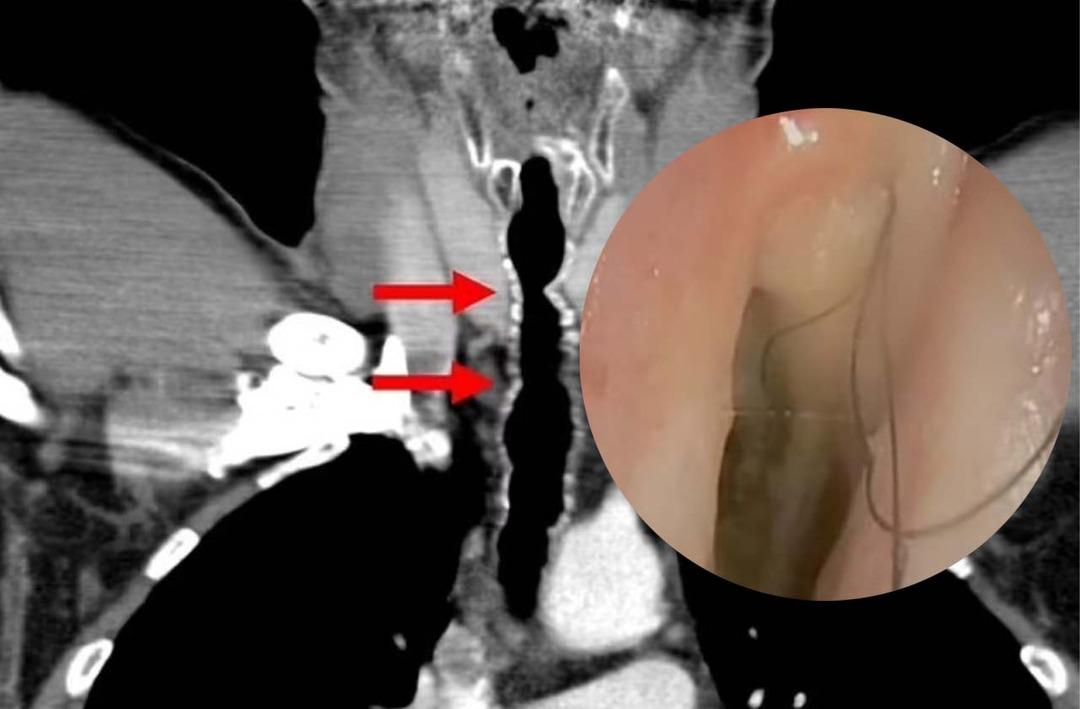

Sağlık görevlileri solunum yollarına küçük bir kamera göndererek inceleme yapmaya karar verdiler ve burada boğazında birkaç koyu renkli kıl çıktığını keşfettiler. Başlangıçta doktorlar tüyleri almayı başardılar ve bu da adama geçici bir rahatlama sağladı.

Saçların bakterilerle kaplandığı tespit edildikten sonra kendisine antibiyotik verildi. Ancak ne yazık ki saçlar sonraki 14 yıl boyunca her yıl saat gibi yeniden çıkmaya devam etti.

Talihsiz adama endotrakeal kıllanma veya boğazda kıllanma adı verilen son derece nadir bir durum teşhisi konuldu. Kesin olarak söyleyemeseler de doktorlar saç büyümesinin muhtemelen sigara içme alışkanlığından kaynaklandığına inanıyorlar.